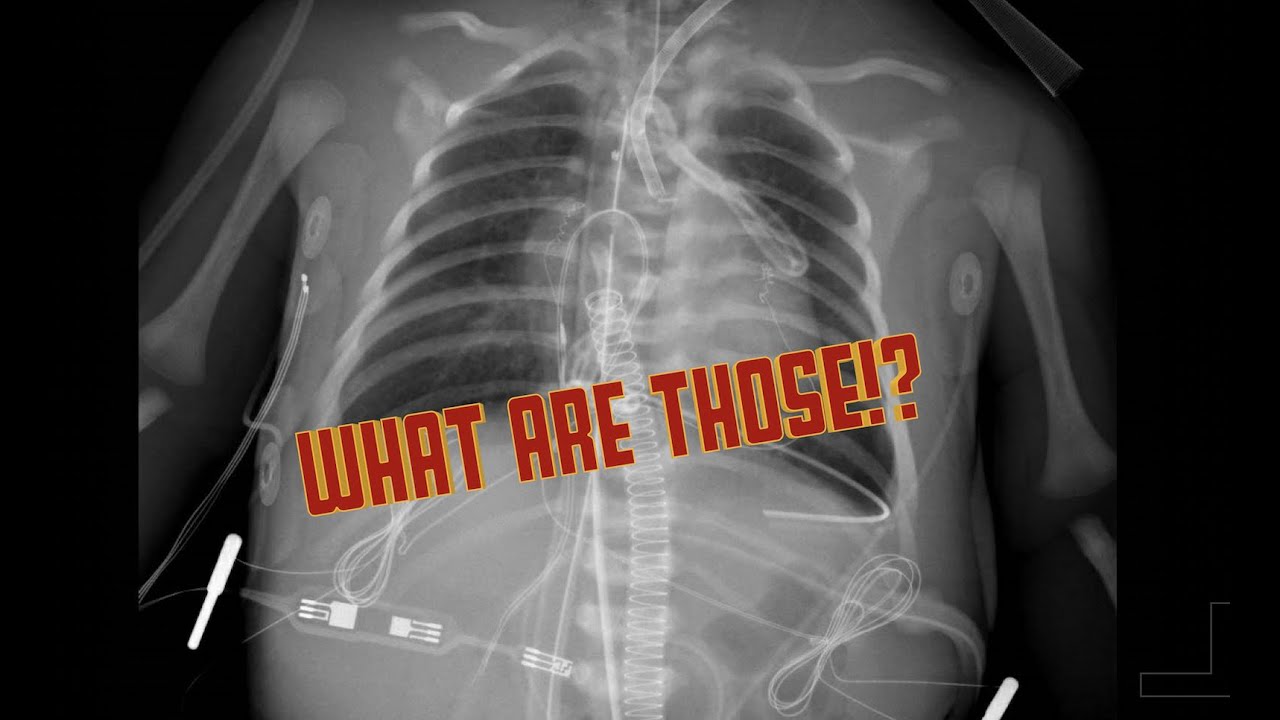

Lines and tube on CXR in the CICU

In this video we review all the lines, tube, devices and other things you may see on x-rays in the pediatric cardiac intensive care unit. This list is not comprehensive, but covers the most common things you will see.

This video is for educational purposes only and should not be used for medical decision making.